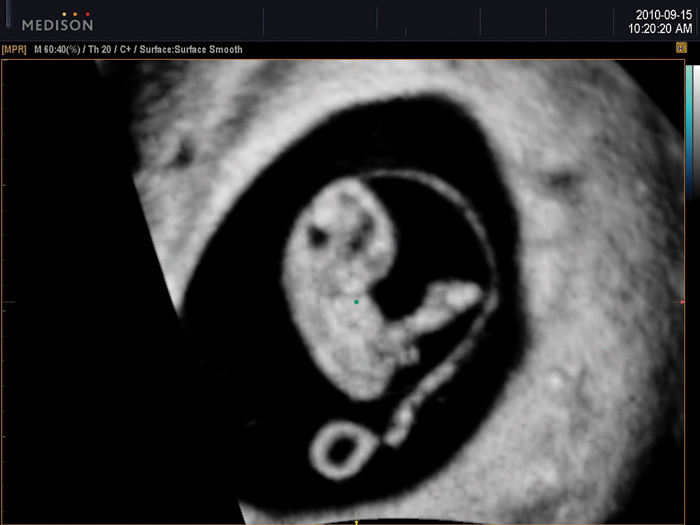

Additional effect of HDVI™ and OVIX™

HDVI™ image has amplified effect if used in conjunction with OVIX™(Oblique View eXtended). OVIX™ reduces noise and increases contrast by compounding multiple images. The pictures show the synergy of HDVI™ and OVIX™ when they are used together.